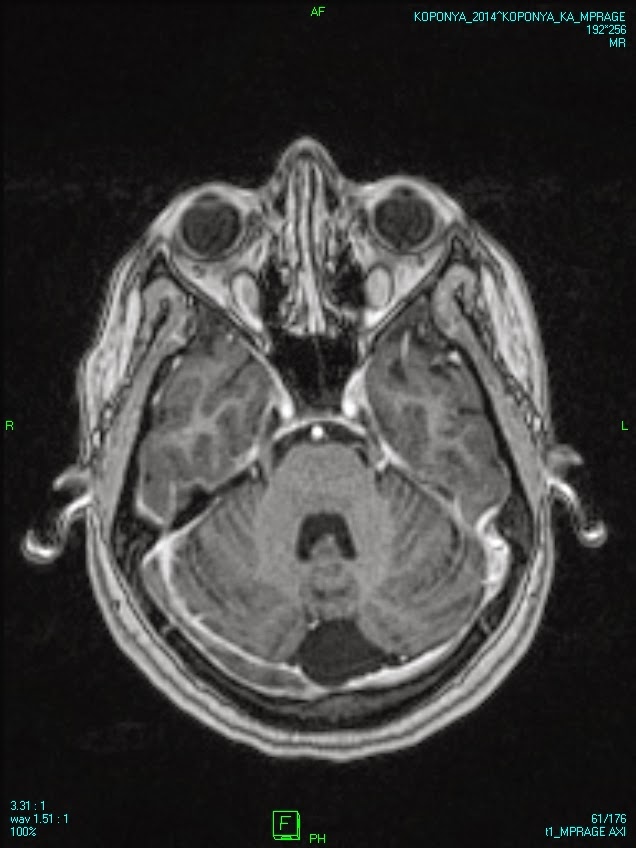

Dural venous sinus thrombosis Szerző: admin | szept 10, 2014 | Brain, Vascular | Nincsenek hozzászólások oral contraceptive in the medical history widened right transverse sinus without total obstruction affected sigmoid sinus on the right 00000815444